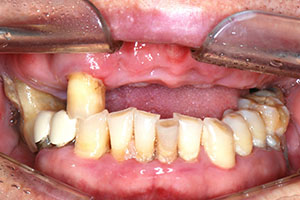

치료증례 전후사진

Before & After

a9db3067cff1c27c28aa713ee7f36abc_1698976199_9893.jpg